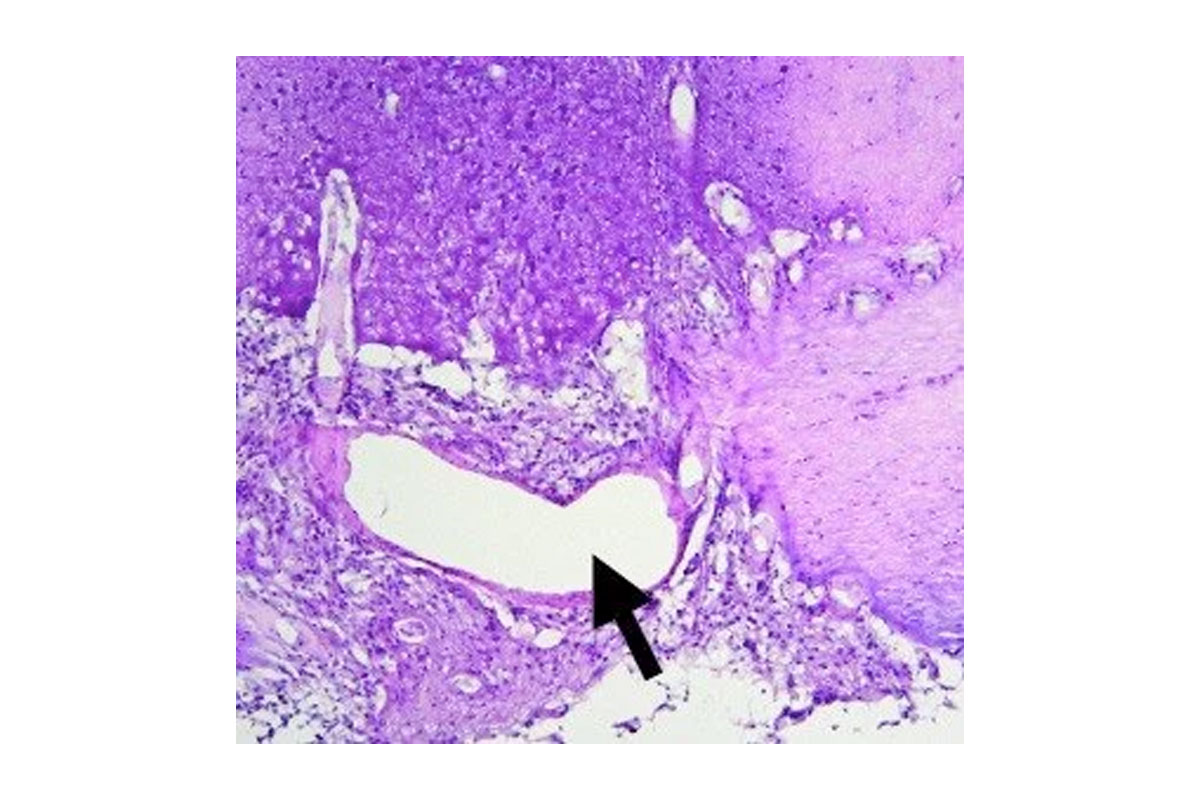

Histological section of a DIPG like tumor formed by engineered human ES cell progeny/ Arrow shows the basilar artery.

Recent sequencing data have demonstrated that pediatric brainstem gliomas (DIPG) are characterized by mutations in histone genes, namely single amino acid substitutions in the tails of H3.3. While a role for post-translational histone modifications in cancer is well recognized, this was the first time mutations in a histone gene were identified as potential drivers in tumors. Key features of K27M-mutated DIPGs are the restricted developmental window during which they emerge [mean age at diagnosis is 8 years] and their specific midline location, which implicate a developmentally early and anatomically specific cell of origin. We postulated that human ES neural progeny might present an ideal candidate to model these tumors. In a recent publication in Science4 we demonstrate a cell context specific tumorigenic effect by H3.3K27M. The transformed cells were capable of initiating large tumors upon grafting in the brainstem of immunodeficient mice. Expression of H3.3K27M in neural precursors led to a developmental resetting to an earlier more primitive stem cell state, thus providing some insight into the biological basis of tumorigenicity by these tumors. In addition, we adapted hES derived neural precursors and their transformed counterparts to an epigenetic drug screen. Selecting for drugs with low IC50 and no negative impact on the normal cells, we identified and validated a menin inhibitor as a potential therapeutic agent against these tumors. Ongoing work is focused on the developmental of a therapeutic strategy for DIPGs as well as on dissecting the biology of histone mutations in tumors. We are also interested in expanding human pluripotent stem cells as a platform for modeling tumors.